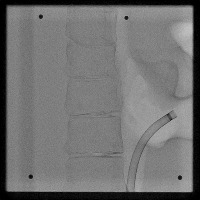

Healthcare Monitoring: "Cath" can be used in a real-time monitoring system within healthcare facilities. It can identify the position and type of a catheter tip in an x-ray, greatly helping healthcare professionals to assess the situation of patients having a lumbar puncture or spinal catheter implantation.

Medical Diagnosis: "Cath" can be used in the diagnosis of possible complications associated with catheter placements. Early detection of catheter displacement can prevent further complications.